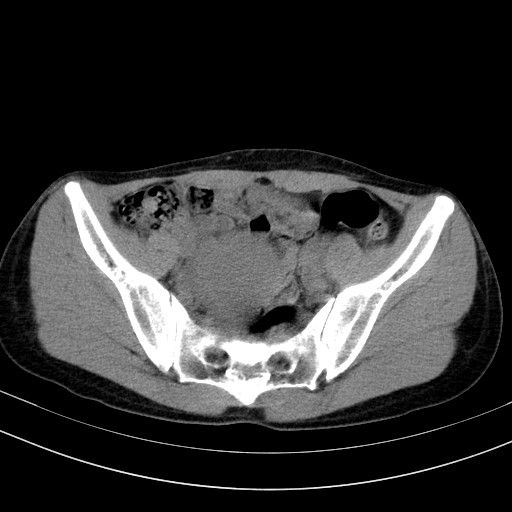

以下是引用随光逐影在2009-4-7 8:17:00的发言:[br]考虑宫颈占位性病变(宫颈癌?);建议行进一步检查。

以下是引用jiangjing在2009-4-7 16:46:00的发言:[br]宫颈增大,结构不清,右侧附件区可疑囊样占位,建议增强及mri 检查